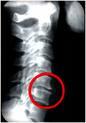

Como médico de la columna vertebral he visto muchos tipos diferentes de problemas relacionados con trabajo y el deporte. Los problemas más comunes son, la hernia discal, lumbago, ciática, y por supuesto el desgaste (la artrosis) Los costaleros están afectando gravemente su columna y se puede evitar sin tener que renunciar a la actividad.

Estos costaleros tenian un estado de desgaste avanzado especialmente cosiderando sus edades tan jóvenes.

El desgaste (artrosis) de la columna se cosidera un problema de la edad,

pero esto es parcialmente erróneo e incompleto. El desgaste (artrosis)

se puede interpretar como un tipo de oxidación del tejido donde los

huesos y las coyunturas se dañan progresivamente sobre un largo periodo

de tiempo. La causa principal es la compresión de la columna y el

costalero expone su columna vertebral a una compresión intensa que

afecta la salud de su columna y tiene efectos negativos a lo largo de

toda su vida.